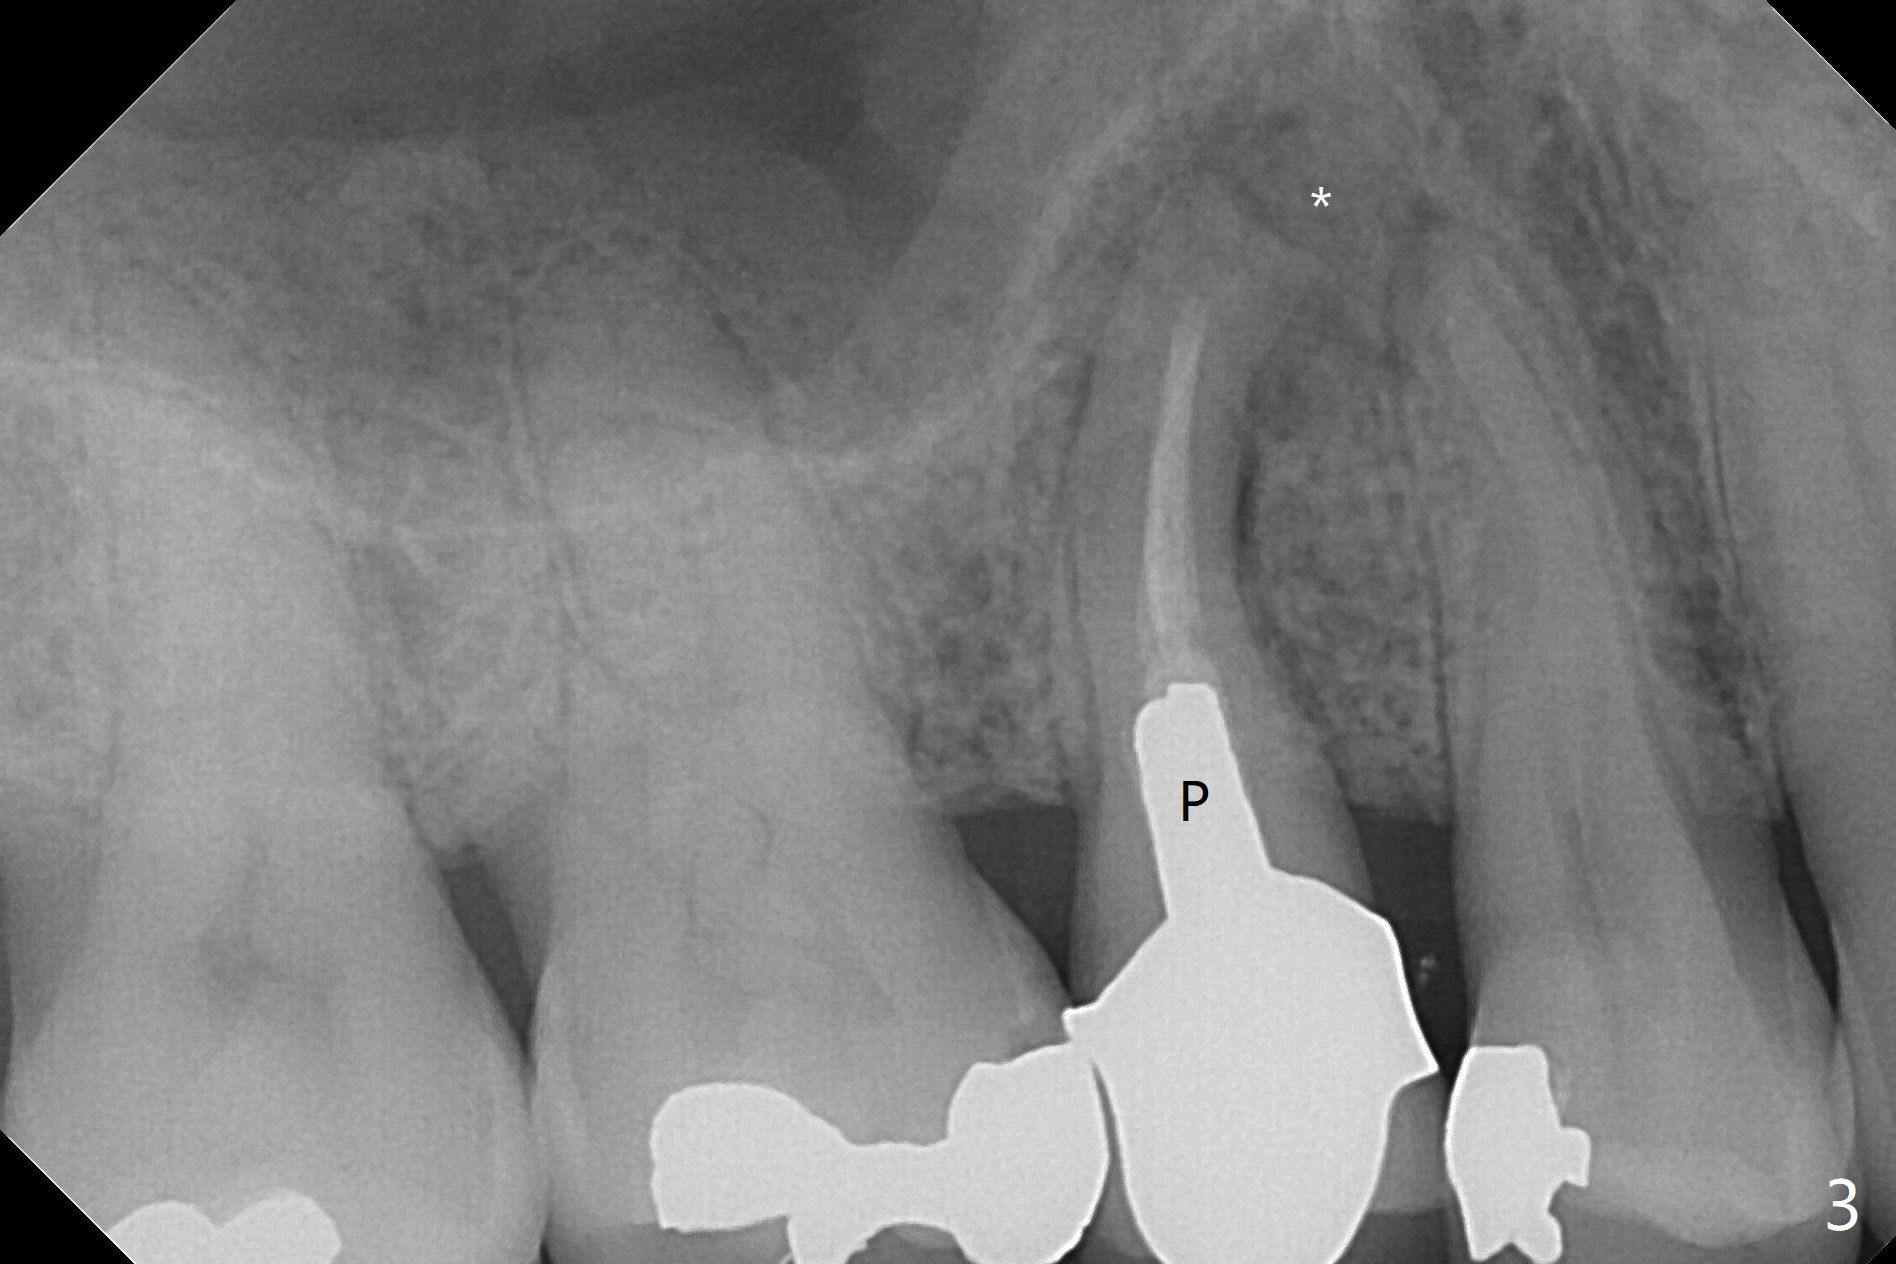

The 48-year-old man agrees to extract the tooth #4 with buccal and palatal fistulae (Fig.1,2 >) and large PARL (Fig.3 *) because of purulent discharge. The large post (Fig.3 P) is most likely associated with a longitudinal fracture. The latter is not noted until postop (Fig.4 <). Intraop finding is large amount of granulation tissue removed from the mesial apical region (Fig.3,5 *). With 10.5 mm offset, Sinus Approach Drill (19 mm) is estimated too short for sinus lift after 3x8.5 mm drill. Without careful repeated check, 2.2x10 and 2.2x11.5 mm drills are used. The sinus floor is perforated, but the membrane seems to be intact. The perforation is too small to insert PRF, but alright for allograft. Then nose blowing test shows that the sinus membrane is perforated, which seems to be repaired after placement of 2 pieces of PRF membrane, followed by another round of allograft (Fig.5 G), which is lifted by a 4x10 mm IS dummy implant. Before placement of a 4.5x11.5 mm final UF implant, allograft is placed in the 3 defective bony areas mentioned above, including the apical mesial one (Fig.6 *). But the final UF implant seems too short with non-satisfactory torque. The latter appears to be solved with the increased length of the implant (Fig.7). The gingiva around the provisional (P) is healthy without fistulae buccal (Fig.8) or palatal 17 days postop (Fig.9). A new abutment with 1 mm longer cuff is seated completely 5.5 months postop (Fig.10 < (no gap), as compared to Fig.7). The lower portion of the mesial defect seems to have been repaired (Fig.11 arrow, as compared to Fig.7). The bone in the sinus seems stable 1.5 years postop (Fig.12). There is no crestal bone loss 4 months post cementation (Fig.13). Return to Upper Premolar Immediate Implant, Trajectory II Xin Wei, DDS, PhD, MS 1st edition 09/27/2019, last revision 04/12/2021